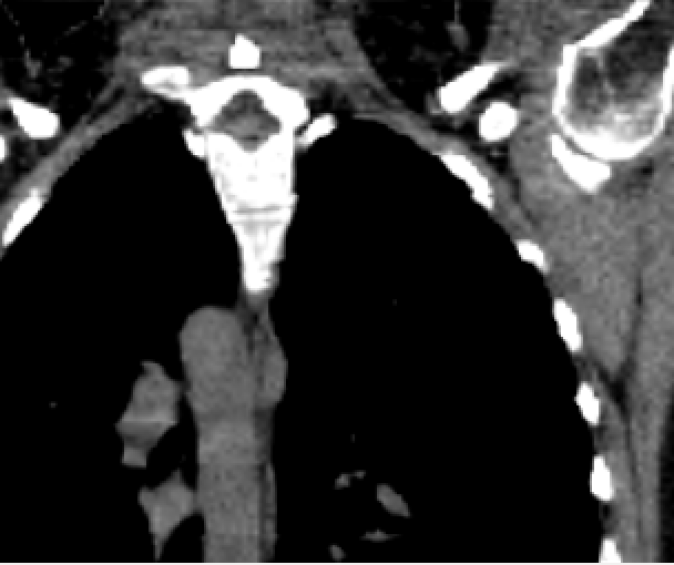

For the 4D reference patient, a 4D-CT data set of the thorax and upper abdomen with 14 respiratory phases (512 462 voxel to 13 mm) and a spirometry signal were used (Fig. 2). The new patient is represented only by a static 3D CT data set (512 318 voxel to 13 mm).

The mean DICE coefficients of the single-atlas registration of the liver and lung masks to the new static patient yield satisfying values of 0.860.12 and 0.960.09. Note the clearly different scan ranges of the data sets (Fig. 2a). The animation of the relevant structures is shown as an example in Fig. 3, using a variable real breathing signal of the target patient (Fig. 2b). In the puncture-relevant liver region, the patient’s breathing states are simulated plausibly for the 4D reference patient (Fig. 3) and, more importantly, the 3D patient (Figs. 4, 5), to which the motion model of was transferred333Demo movie, click here.